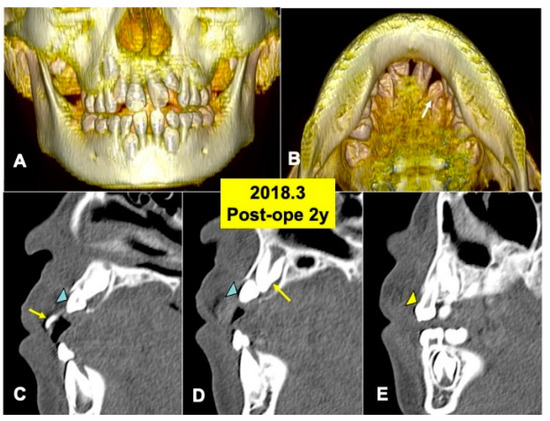

Gross View and Radiographic Evaluation after Surgery